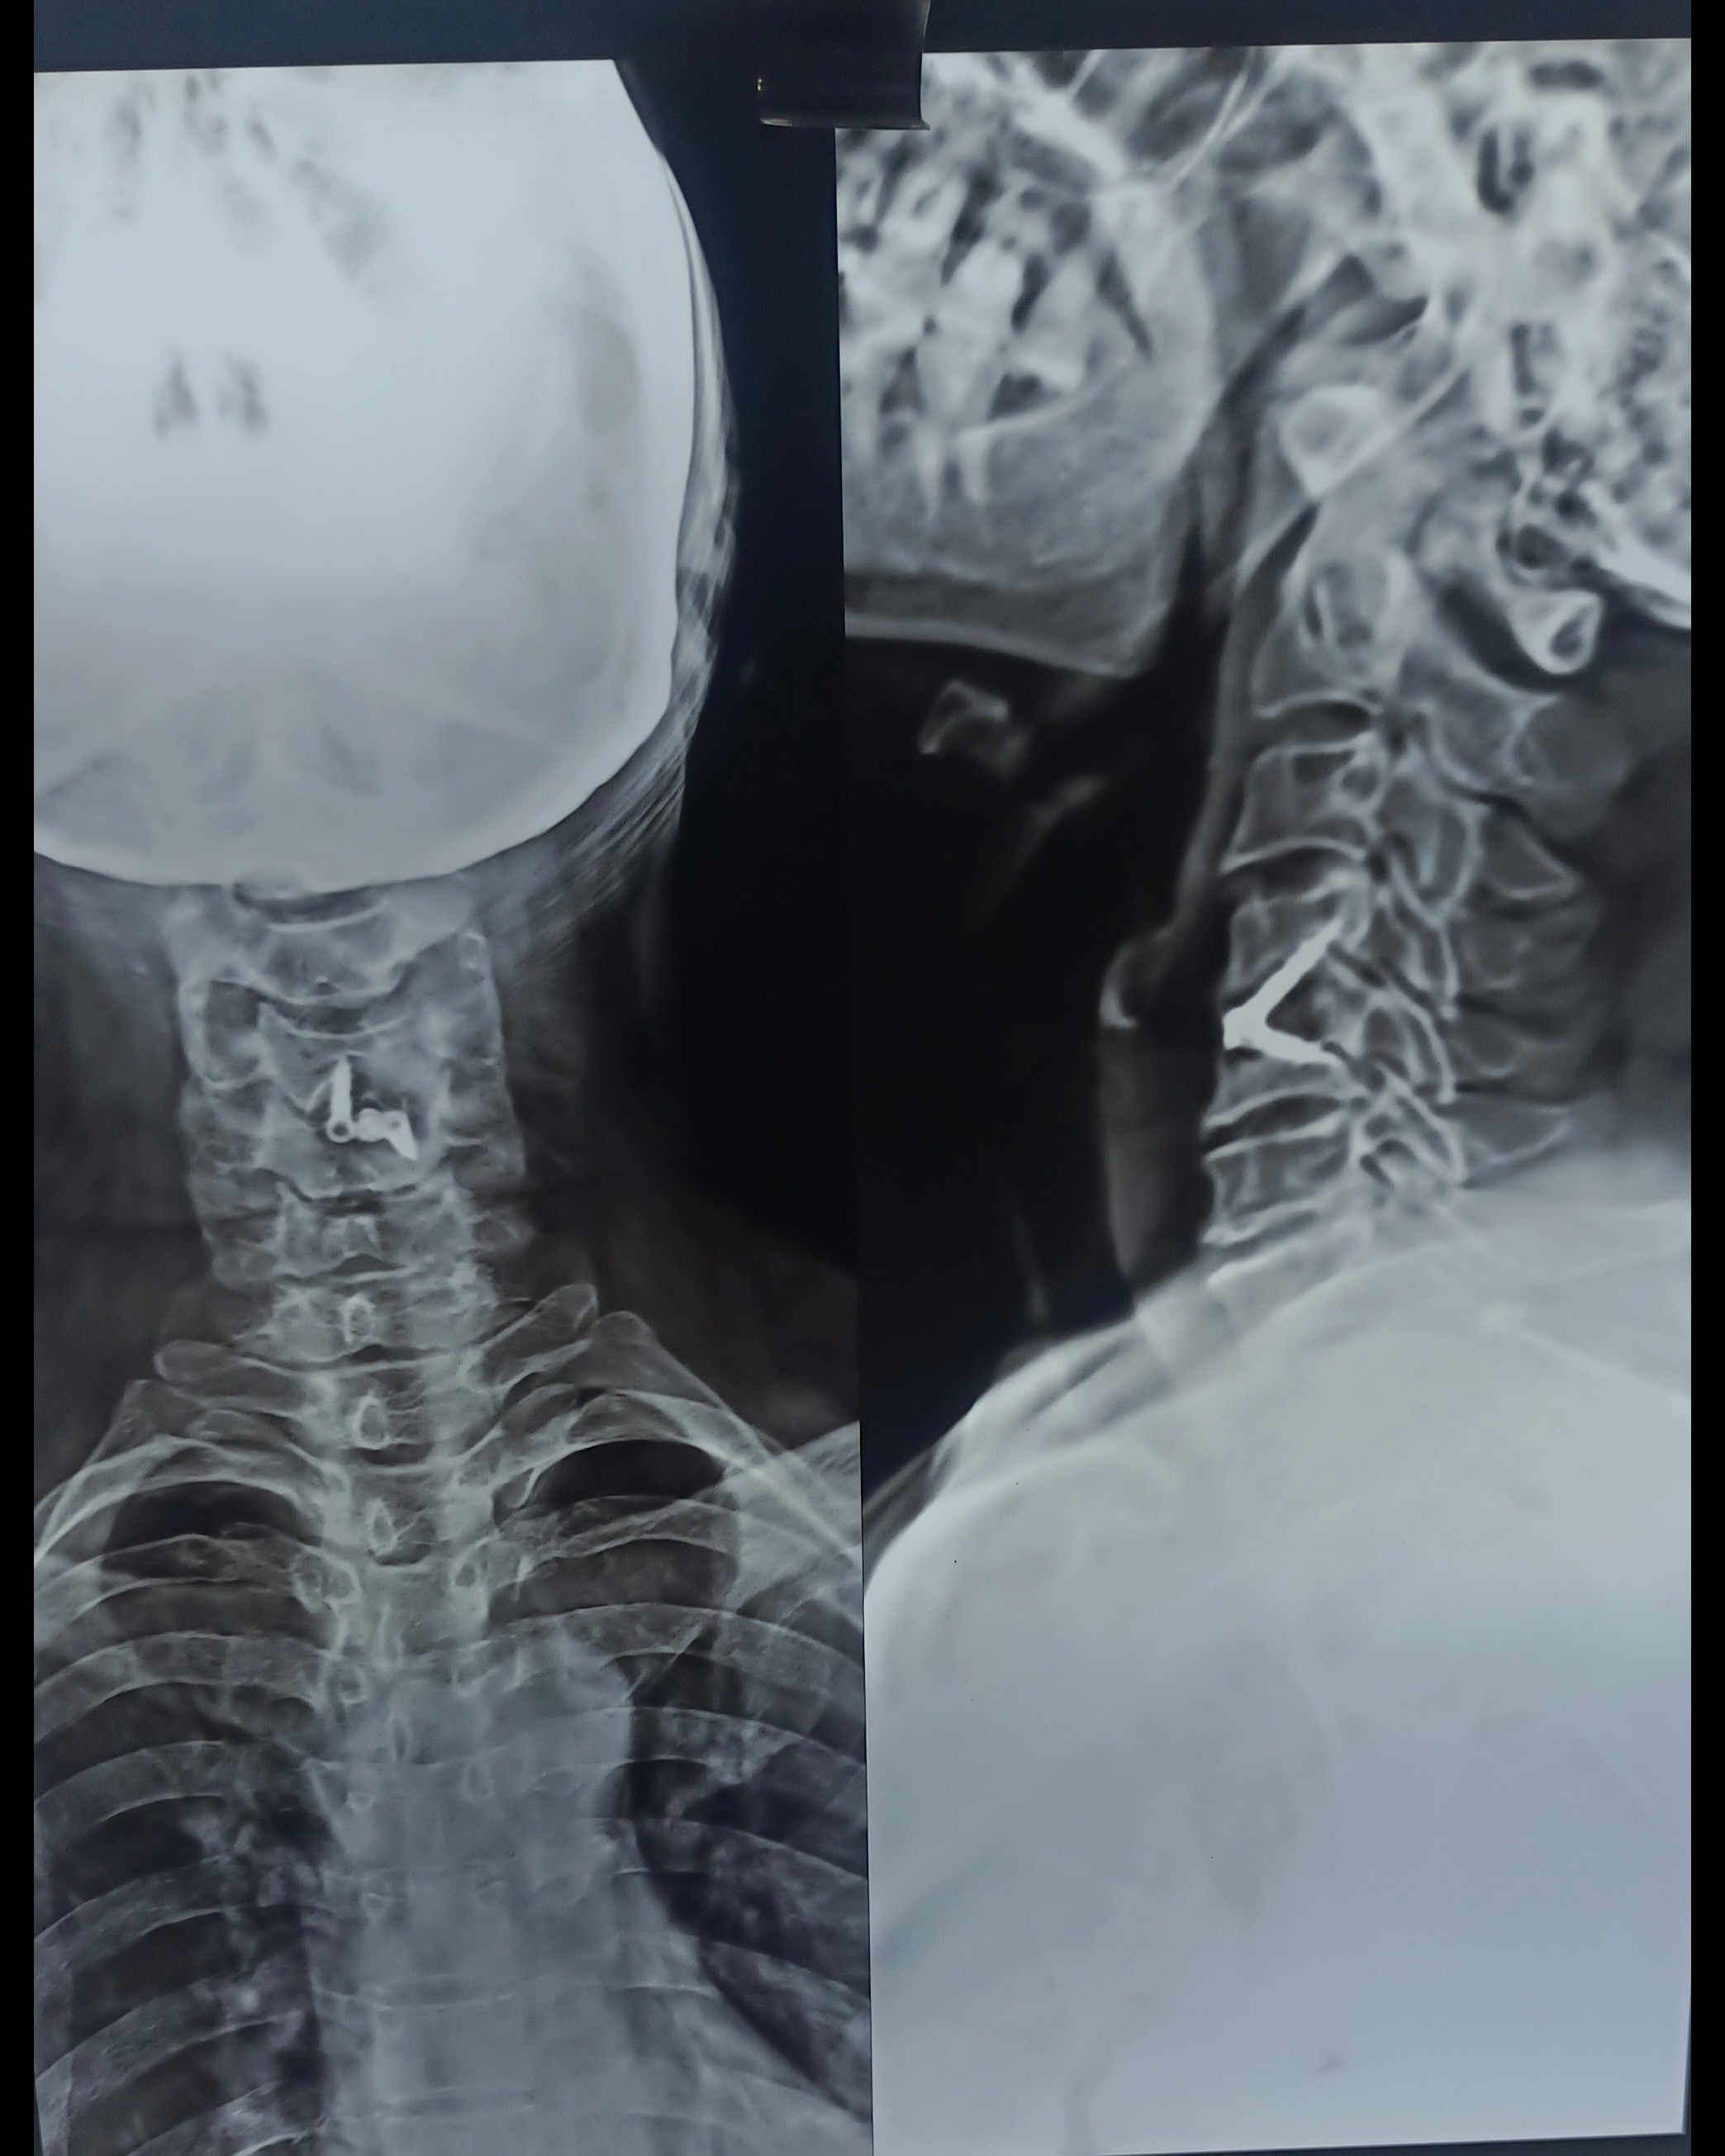

Are you searching for Spine Surgery Specialist in Pune ? Spine Surgery Doctor in Pune ? Spine Surgery Specialist In Shivaji Nagar ? Cervical Spine treatment in Pune ? Neck Surgeon in Pune ? Disc prolapse Treatment in Pune ? Meet Dr. Nitish Agarwal Best Spine Surgeon in Pune, aundh, Shivaji Nagar, Deccan, Kothrud, Erandwane, Dattawadi, Swargate, FC road, Karwe Road This patient having Neck Pain, Left Upper Limb Radicular Pain, Left Leg pain, Difficulty during Walking. She is Diagnosed with C4-C5 Disc Prolapse / Cervical Disc Prolapse with Severe Spinal Cord Compression with Cord Myelomalacia with Nerve Root Compression We did Anterior Cervical Discectomy and Fusion Surgery for her. We removed Complete Disc and Osteophytes and freed the Nerve Roots along with Decompression Of Spinal Cord. We stabilised her spine with Standalone Cage / New Artificial Peak material Disc and Titanium Screws. Patient starts walking from next day of Surgery. All her pain and difficulties gone. She is very happy with the Surgery and Results